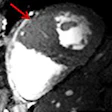

7T MRI detects abnormal thickening of heart tissue